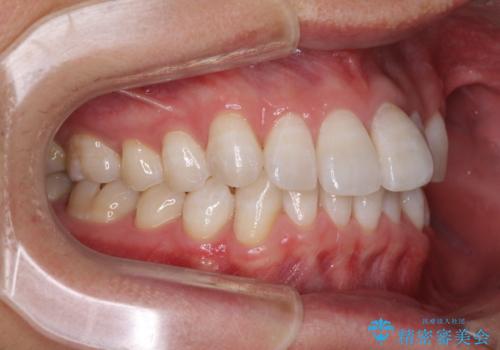

前歯のデコボコを治したい インビザラインによる矯正治療

上下顎ともに歯列全体の後方移動とIPR(歯と歯の間を削る)によってデコボコが解消するように設計し、インビザラインにより治療を行うこととしました。

矯正治療後、前歯の形と色が気になるとのことでしたが、大分前に失活している(神経が取り除かれている)歯であり、その影響で変色しているため、オールセラミッククラウンによる補綴治療をおすすめいたしました。